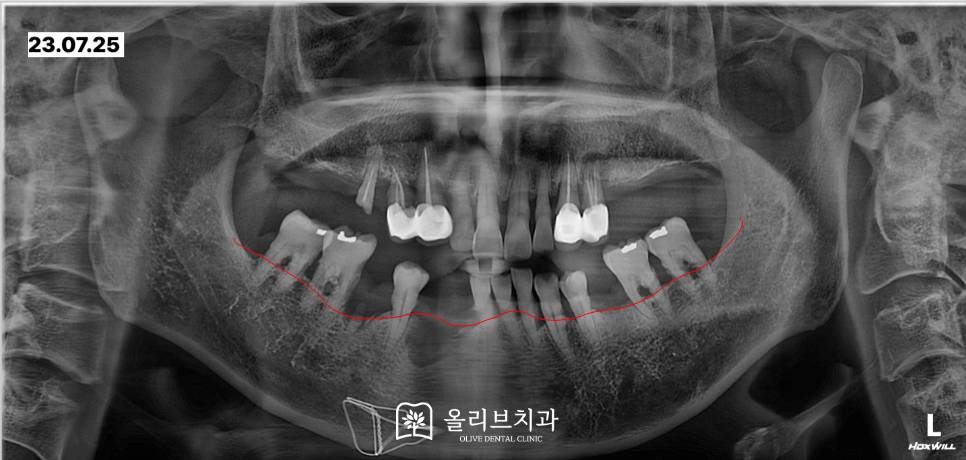

전체적인 상태를 체크하기 위해서 촬영한 파노라마 x-ray입니다. 위쪽의 큰 어금니들은 내원하셨을 때 이미 상실된 상태였습니다.

상악 우측 작은어금니는 뿌리만 남아있으며 상악 좌측 작은 어금니에는 뿌리 끝 염증이 발생해 있었습니다.

x-ray상에서 보면 하악의 치아가 위치한 치주부분들이 좋지 않아 잇몸뼈가 많이 내려간 상태여서 치아가 전반적으로 흔들리는 상황이었습니다.

입 안에서도 살펴보면 남아있는 치아에는 치석이 많이 쌓여있어서 치주상태가 좋지 않은 것을 확인할 수 있습니다.